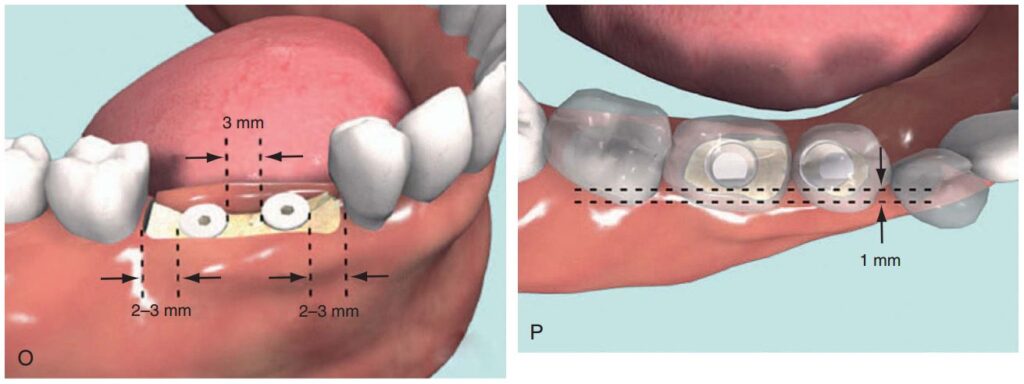

Dụng cụ hướng dẫn định vị Implant

Giúp xác định đúng vị trí đặt Implant và lựa chọn đường kính Implant tối ưu nhất (H2.18). Bộ hướng dẫn ITT gồm có:

– Tấm Titan, giúp hướng dẫn đường kính và vị trí của 1 – 2 Implant.

– Pin đo đạc có phần mở rộng, giúp hướng dẫn đường kính và vị trí Implant ở bệnh nhân không răng.

– Pin song song, để xác định độ song song của Implant.

– Cán của tấm Titan, giúp cầm nắm và đặt tấm Titan vào trong miệng 1 cách an toàn.